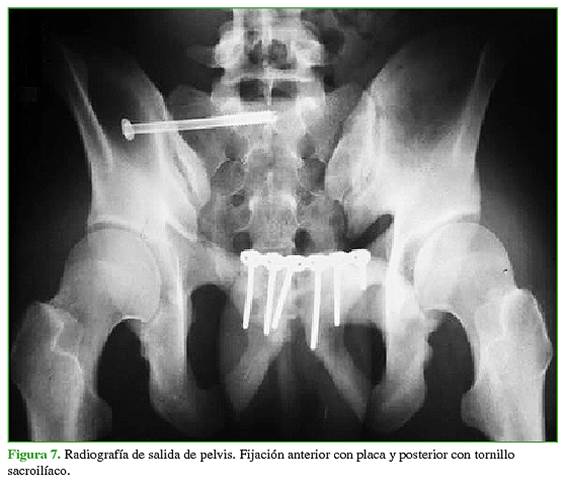

Los tipos de fijación analizados se dividieron en dos grupos. El primer grupo incluyó a los pacientes operados con fijación anterior con placa mediante un abordaje de Pfannenstiel y percutáneo sacroilíaco. Al segundo grupo lo conformaron los pacientes operados únicamente con fijación anterior con placa por medio de un abordaje tipo Pfannenstiel (sin fijación posterior), más los operados con fijación externa anterior y percutánea sacroilíaca. La división en grupos se realizó de esa manera para comparar el tratamiento más aceptado en la actualidad y recomendado en la bibliografía (fijación anterior con placa y posterior percutánea), con el resto de los tratamientos realizados. El tratamiento para cada paciente se seleccionó según las características de cada uno de ellos, sus enfermedades y lesiones asociadas, y en conjunto con los demás servicios tratantes. Además, los primeros pacientes de la serie habían sido tratados solo con fijación anterior, en los últimos años de la serie, se agregó la fijación posterior percutánea. La fijación anterior se realizó, en todos los casos, con una placa de reconstrucción o una placa DCP de 3,5 mm, según la disponibilidad. La mayoría de los pacientes fueron operados con placas de reconstrucción de 3,5 mm y dos, con placas DCP 3,5 mm. Los tornillos sacroilíacos utilizados fueron de 6,5 mm y 7 mm.

A cinco pacientes (21,73%) se les realizó únicamente fijación anterior con un abordaje tipo Pfannenstiel, 13 (56,52%) fueron operados mediante fijación anterior y percutánea sacroilíaca (Figuras 5-7) y cinco (21,73%), mediante fijación externa anterior y percutánea sacroilíaca. La reducción posoperatoria fue <1 cm en 16 pacientes (69,57%). Cinco (21,73%) sufrieron una infección del sitio quirúrgico.